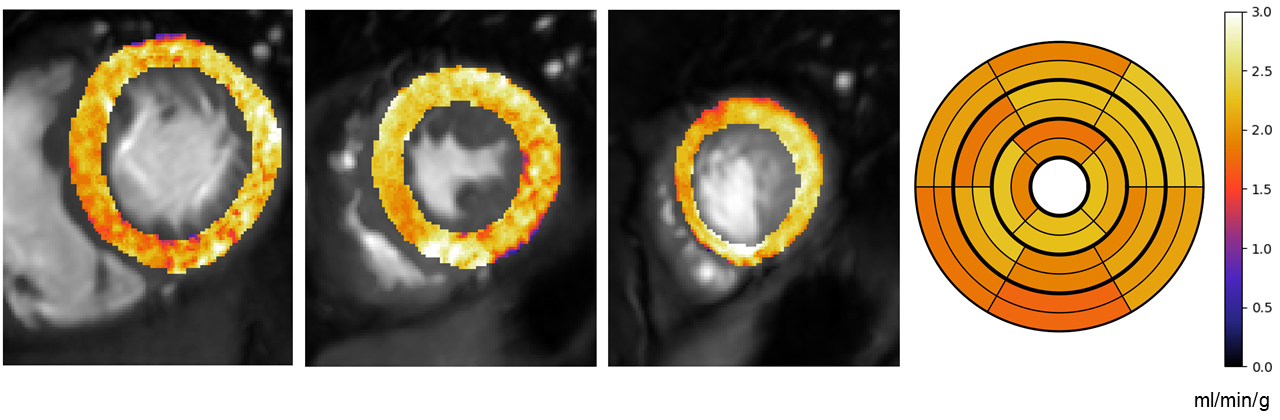

\printthesisindex